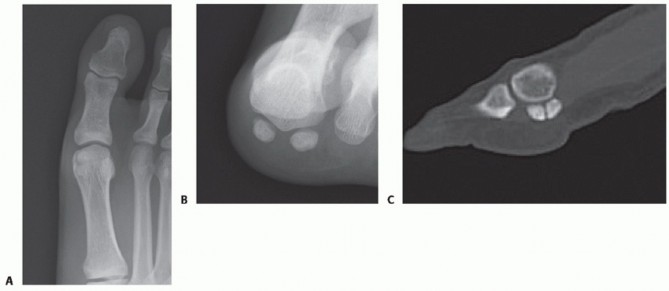

Sesamoid oblique and tangential (“skyline”) views are useful to evaluate sesamoid fracture displacement (FIG 4A).

A longitudinal computed tomography (CT) scan of the foot has been shown to be very effective in demonstrating sesamoid stress fracture in difficult settings4 (FIG 4B).

FIG 4 • Radiologic examination of sesamoid fractures. A. Conventional radiographs demonstrating horizontal sesamoid fracture dislocation. B. CT scan shows fracture line of chronic painful sesamoid, which was not visible on conventional radiographs.*

Radiographs suggest medial (tibial) sesamoid fracture (TECH FIG 3A,B).

CT scan demonstrates transverse fracture line with a subacute/chronic appearance (TECH FIG 3C). - Exposure

- TECH FIG 3 • A 22-year-old man with right medial (tibial) stress fracture failing to heal with nonoperative measures. A. AP view. Note medial (tibial) sesamoid with a gap and slight hallux valgus. B. Sesamoid view does not demonstrate this fracture. C. CT scan demonstrates transverse fracture line with a subacute/chronic appearance.